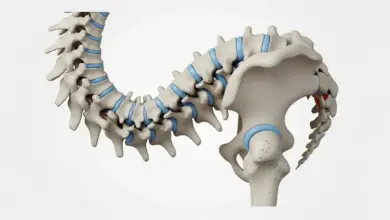

Tumor na coluna é uma massa formada por crescimento anormal de células. Ele pode surgir:

- No osso da vértebra (tumores ósseos primários).

- Dentro do canal vertebral, próximo da medula ou das raízes nervosas.

Nem todo tumor é câncer. Tumores benignos existem e podem ser controlados, mas ainda podem causar dor, fraturas por fragilidade e compressão nervosa, dependendo do tamanho e da localização.